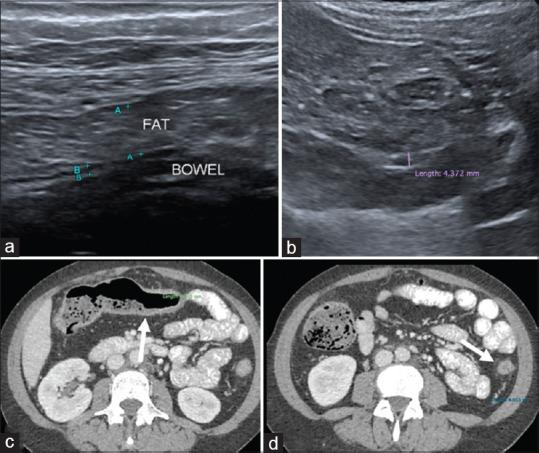

This is a prospective cross-sectional study of IUS performed on IBD patients in a tertiary centre. IUS parameters including intestinal wall thickness, loss of wall stratification, mesenteric fibrofatty proliferation, and increased vascularity were compared with endoscopic and clinical activity indices.

Among the 51 patients, 58.8% were male, with a mean age of 41 years. Fifty-seven percent had underlying ulcerative colitis with mean disease duration of 8.4 years. Against ileocolonoscopy, IUS had a sensitivity of 67% (95% confidence interval (CI): 41-86) for detecting endoscopically active disease. It had high specificity of 97% (95% CI: 82-99) with positive and negative predictive values of 92% and 84%, respectively. Against clinical activity index, IUS had a sensitivity of 70% (95% CI: 35-92) and specificity of 85% (95% CI: 70-94) for detecting moderate to severe disease. Among individual IUS parameters, presence of bowel wall thickening (>3 mm) had the highest sensitivity (72%) for detecting endoscopically active disease. For per-bowel segment analysis, IUS (bowel wall thickening) was able to achieve 100% sensitivity and 95% specificity when examining the transverse colon.